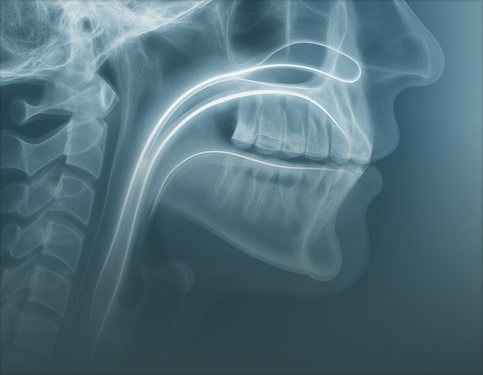

Advanced Report includes annotated images, detailed key findings, and practical clinical recommendations. Choose this option for treatment planning, complex cases, referrals, or when visuals are needed to communicate findings with colleagues or patients and support confident clinical decisions in the final report.